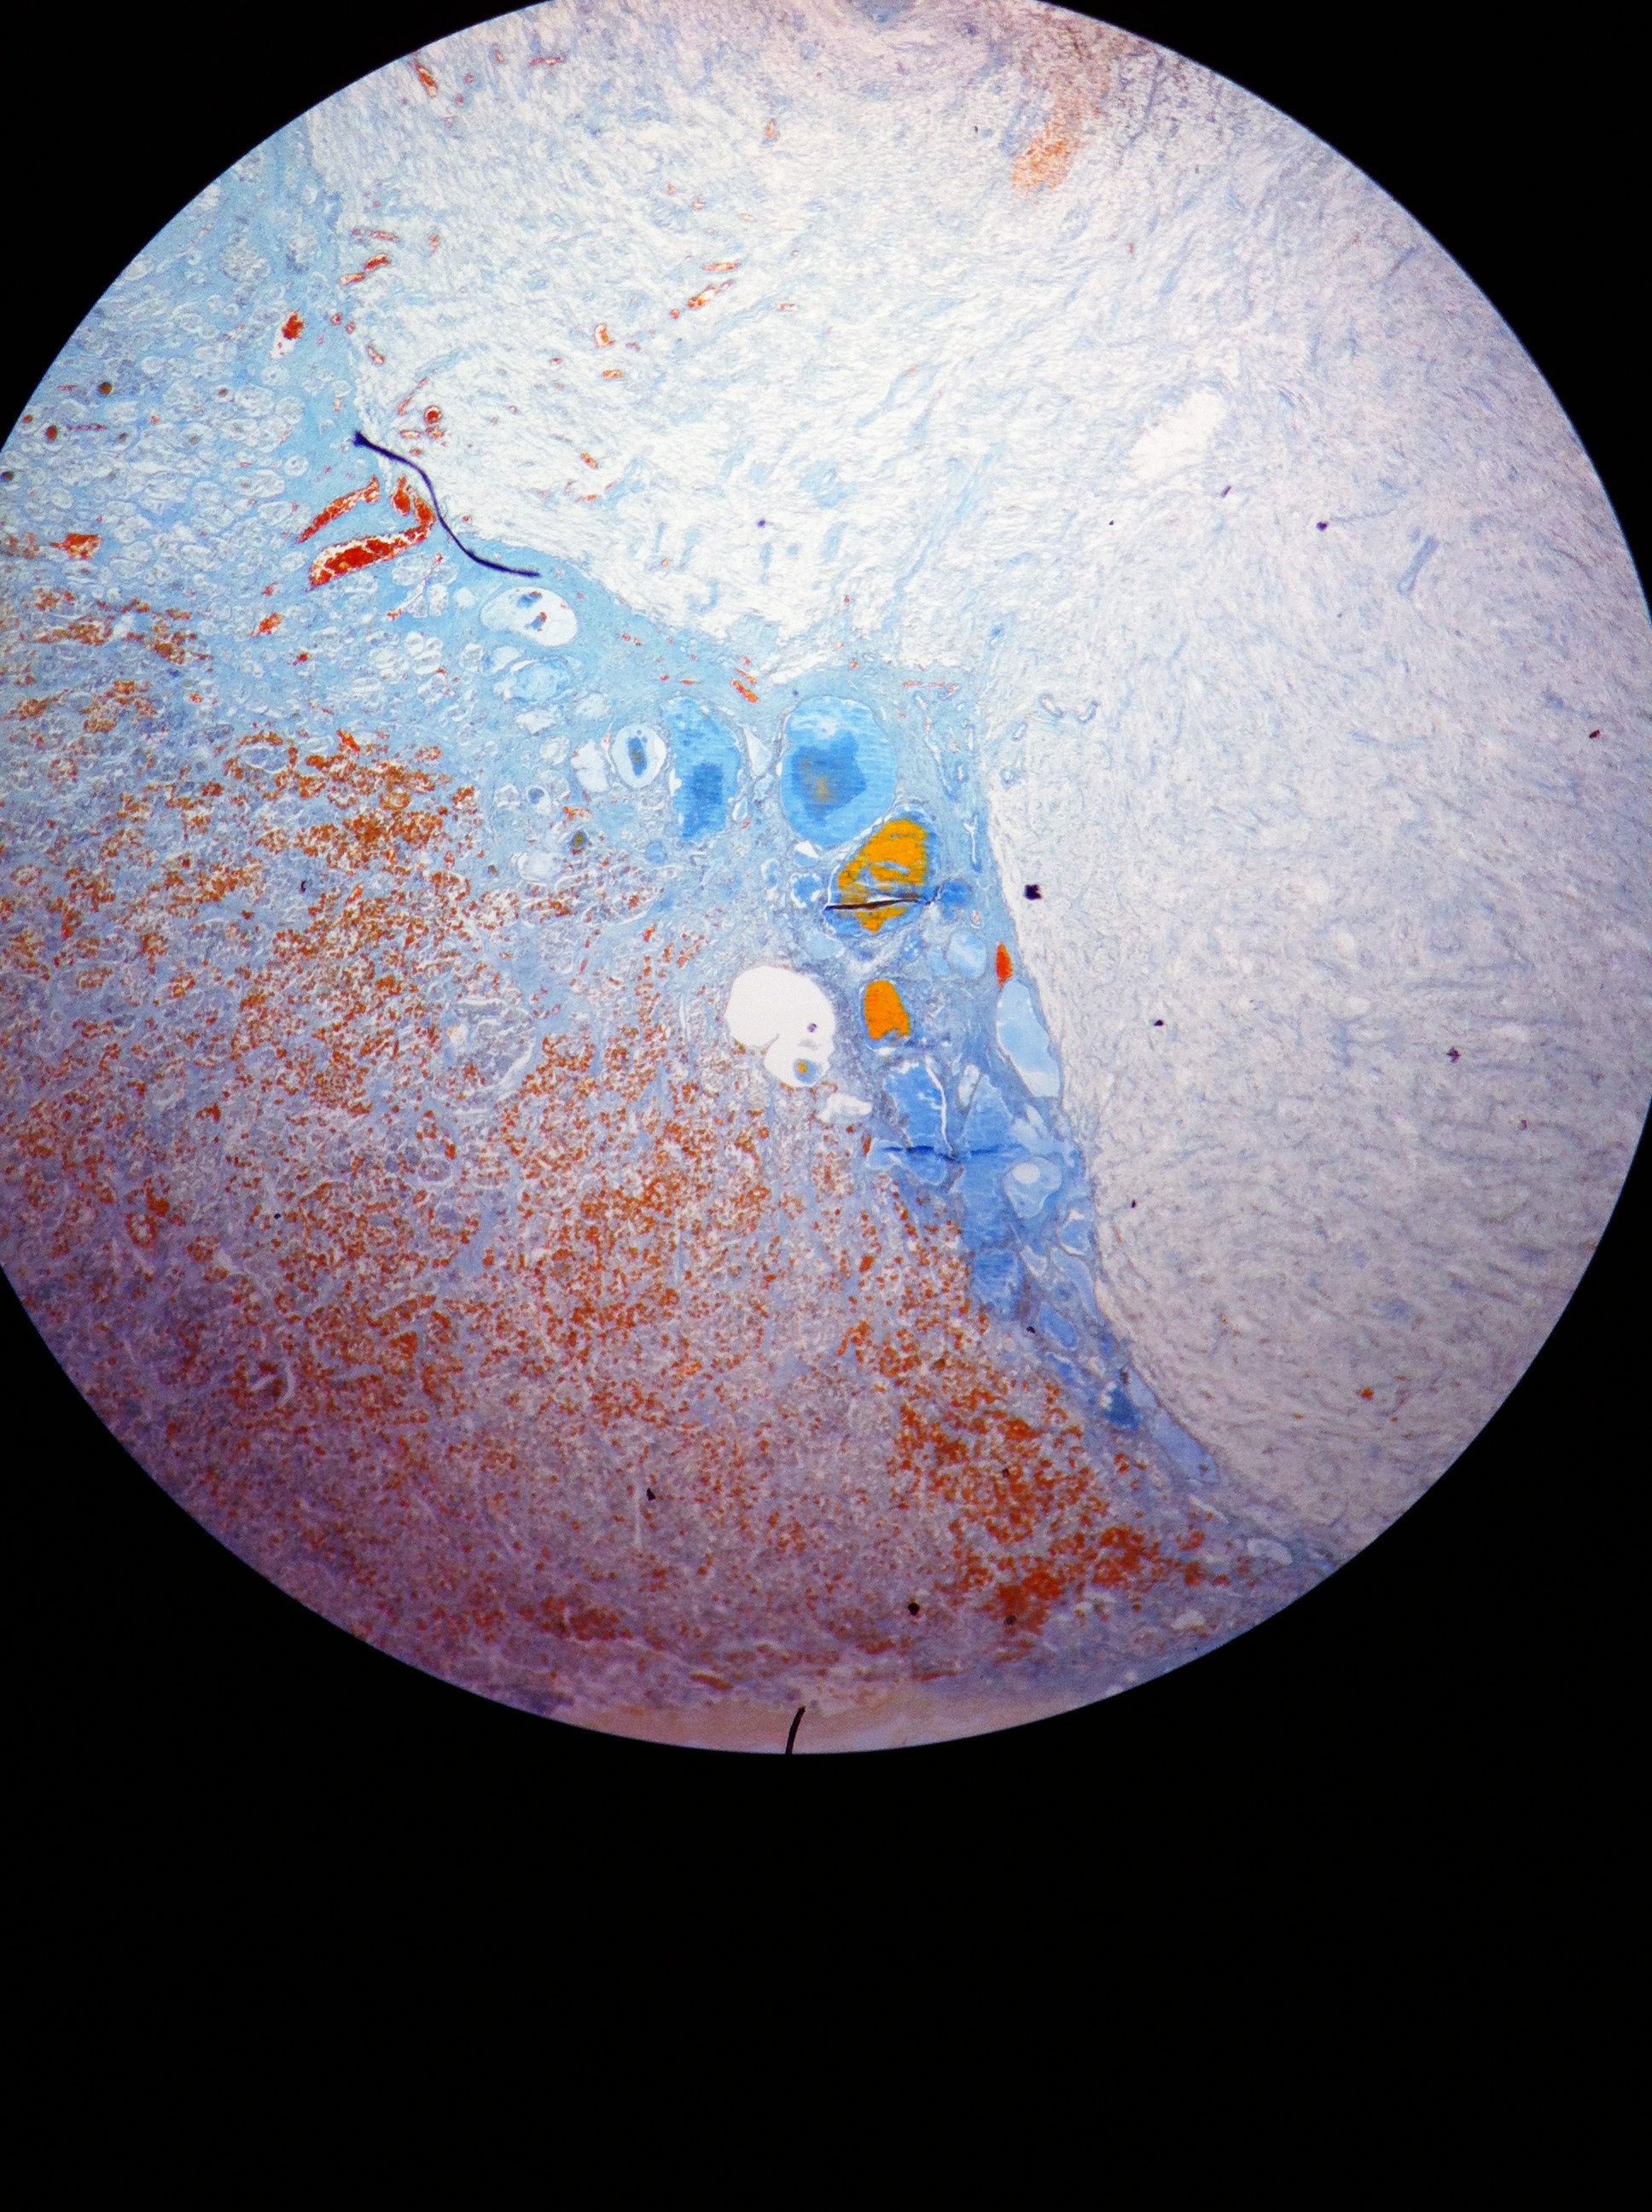

Adrenal Cortex 40X

Adrenal Cortex 100X